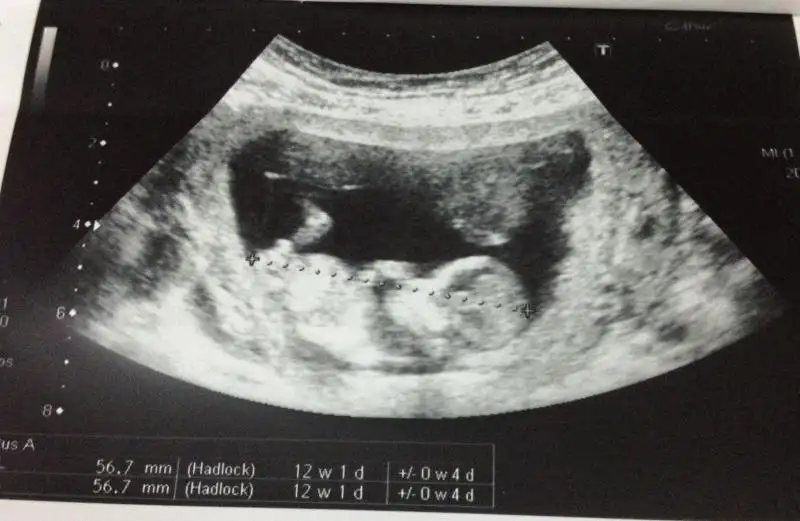

arkadaşlar bu ultrasyon resmide ablama ait ablam şuan 19 haftalık hamile ama dr lar hala net birşey diyemiyorlar belki siz bişiler dersiniz.

$bebeke4.webp $bebeke3.webp $bebeke1.webp $bebeke2.webp

kızlar ne olur cevaplayın=))